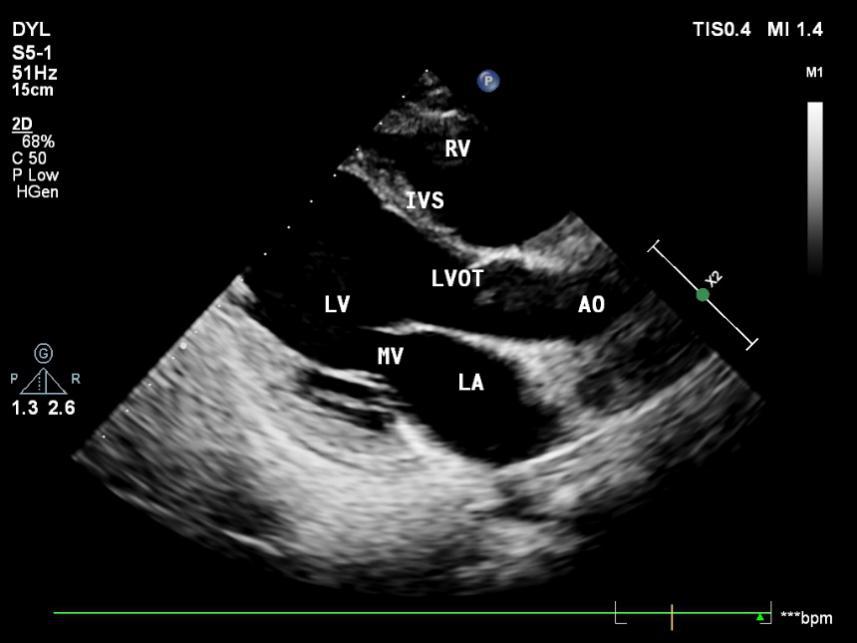

1.1胸骨旁左室长轴切面

胸骨旁左室长轴二维超声胸骨旁左室长轴二维超声

LA:左房 LV:左室 RA:右房 RA:右室;

MV:二尖瓣 TV:三尖瓣 AV:主动脉瓣;

AO:主动脉 LVOT:左室流出道;

IVS:室间隔。